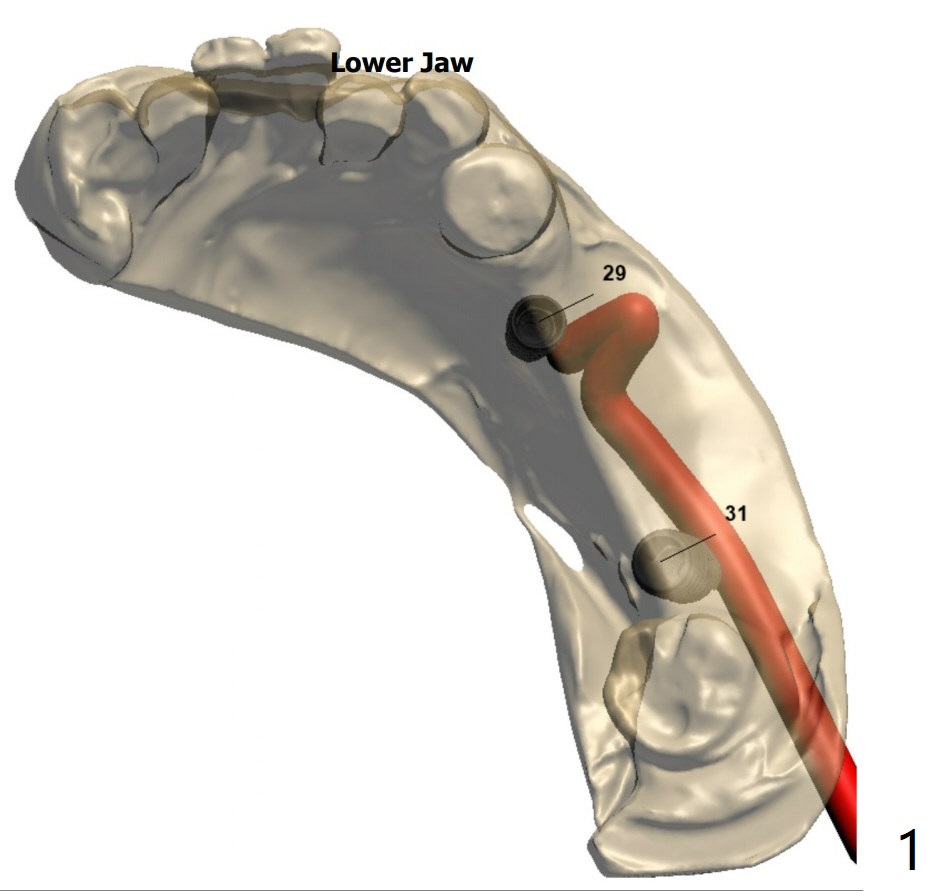

Implant FPD: Design 1

A 81-year-old woman wants to eat well.  #3, 15, 29-31 are missing.